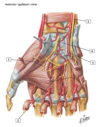

1

1 - Abductor pollicis brevis muscle

1

1 - Flexor pollicis brevis muscle

1

1 - Opponens pollicis muscle

1

1 - Adductor pollicis muscle

1

1 - Abductor digiti minimi muscle

1

1 - Flexor digiti minimi brevis muscle

1

1 - Opponens digiti minimi muscle

1

1 - lumbrical muscles 1 and 2

2

2 - lumbrical muscles 3 and 4